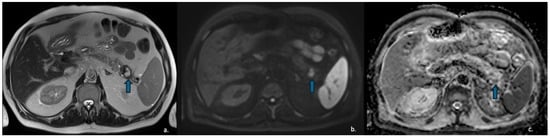

On CECT, cystic PanNETs typically appear as mixed cystic and solid lesions with rim or peripheral enhancement in both the arterial and portal venous phases, reflecting their rich vascular supply—although the arterial-phase enhancement is generally more pronounced. MRI is valuable for evaluating communication with the pancreatic ducts, which is typically absent in PanNETs [66,67] (Figure 11).

Figure 11.

MRI of a 57-year-old man with neuroendocrine neoplasm (NEN) with cystic degeneration involving the pancreatic body (arrow). The lesion appears hyperintense on T2-w-HASTE sequences (a) and demonstrates peripheral rim-enhancement (b). MR cholangiography shows no communication with the main pancreatic duct (c).

Occasionally, certain PanNETs present with ill-defined margins, heterogeneous hypovascular enhancement, and main pancreatic duct dilatation, closely resembling pancreatic adenocarcinoma and complicating differential diagnosis. Nevertheless, this diagnostic difficulty can be overcome through the use of Dual-Energy CT, which facilitates tissue characterization and lesion differentiation [68].